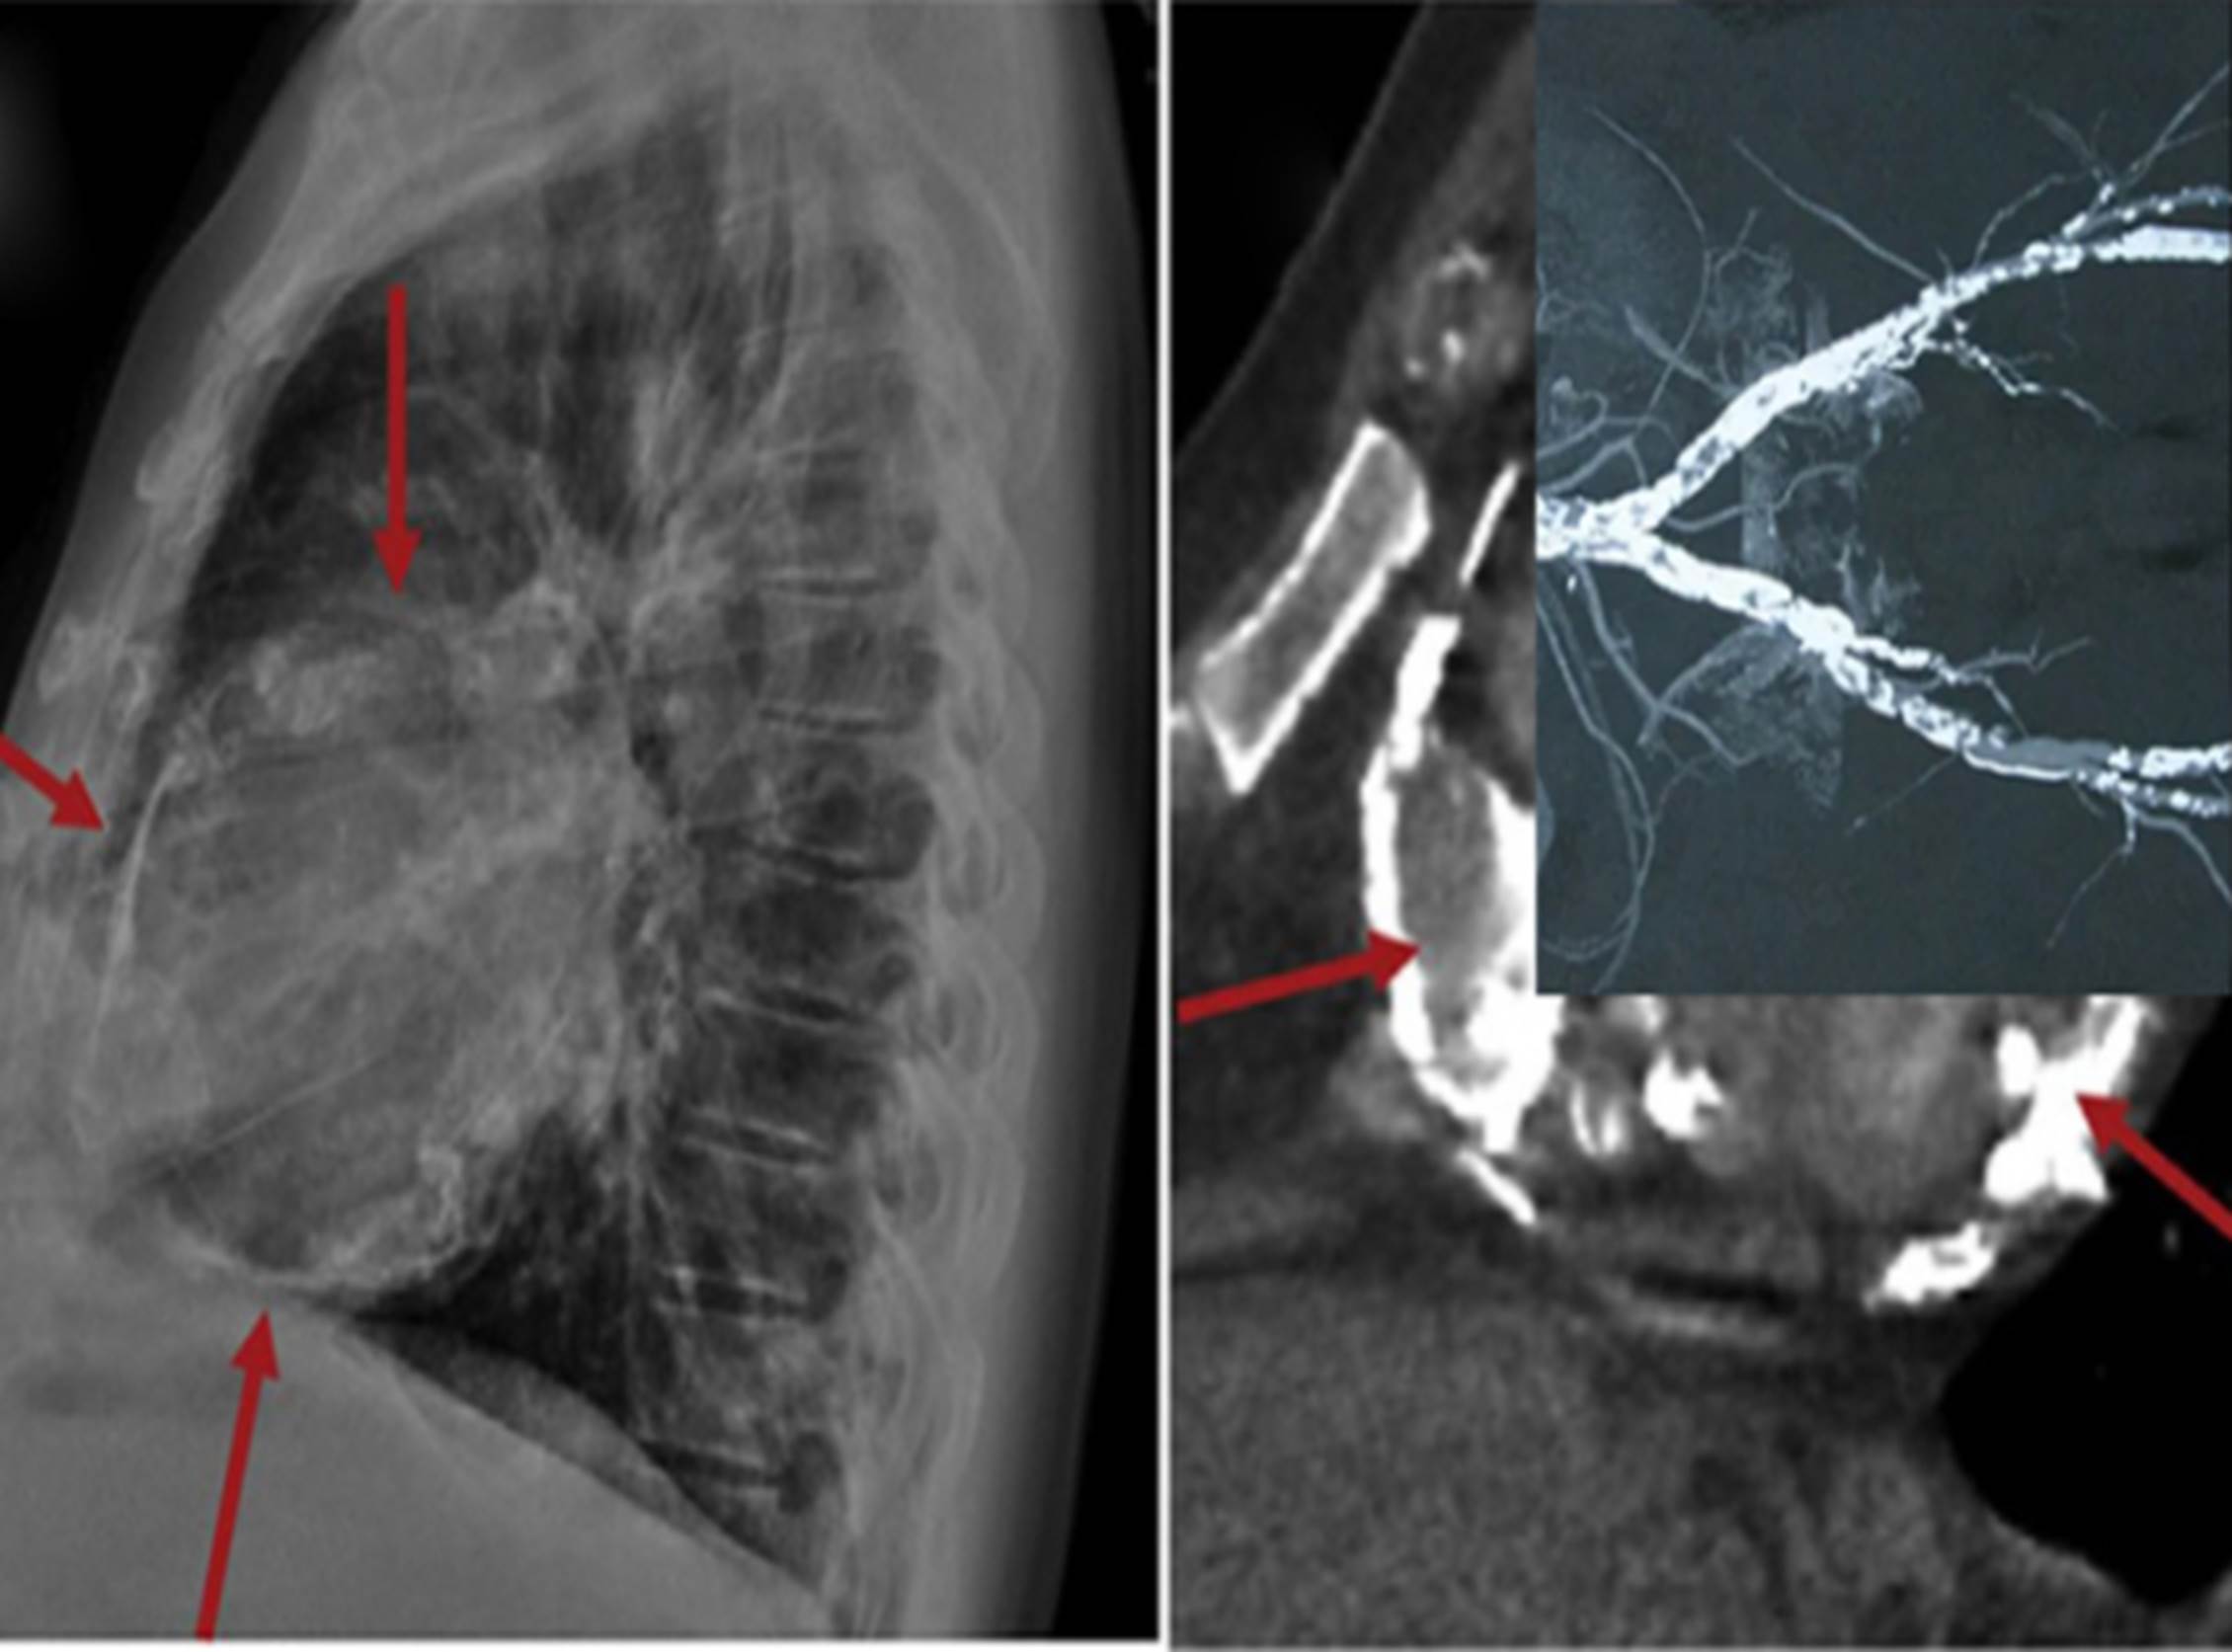

Tại đây, các bác sĩ nhanh chóng kiểm tra các chỉ số về thận của ông nhưng phát hiện vấn đề lần này không nằm ở thận. Dựa trên các triệu chứng lâm sàng, bác sĩ Jiang Shoushan tiến hành chụp X-quang phổi và mạch máu cho ông Chen. Kết quả là tuy không bị nhồi máu cơ tim giống như gia đình nghi ngờ nhưng những mạch máu ở tim của ông bị vôi hóa nghiêm trọng đến bất ngờ.

Vôi hóa mạch máu ở tim có thể được phát hiện thông qua chụp X-quang, cộng hưởng từ (Ảnh minh họa)

Bác sĩ Jiang chia sẻ về ca bệnh này trên chương trình “Cuộc sống khỏe mạnh và tốt đẹp” như sau: “Trong gần 20 năm hành nghề của mình, tôi rất hiếm gặp trường hợp mạch máu tim bị vôi hóa nghiêm trọng đến vậy ở độ tuổi đó. Khi nhìn vào hình ảnh X-quang, chính bệnh nhân cũng phải ngạc nhiên.

Bởi vì những mạch máu của ông đặc, cứng lại giống như ruột của chiếc bút chì. Do vậy, trên phim X-quang chúng trắng xóa và vô cùng rõ nét dù không dùng thuốc cản quang trước đó hay các máy móc hỗ trợ khác trong quá trình phân tích phim.